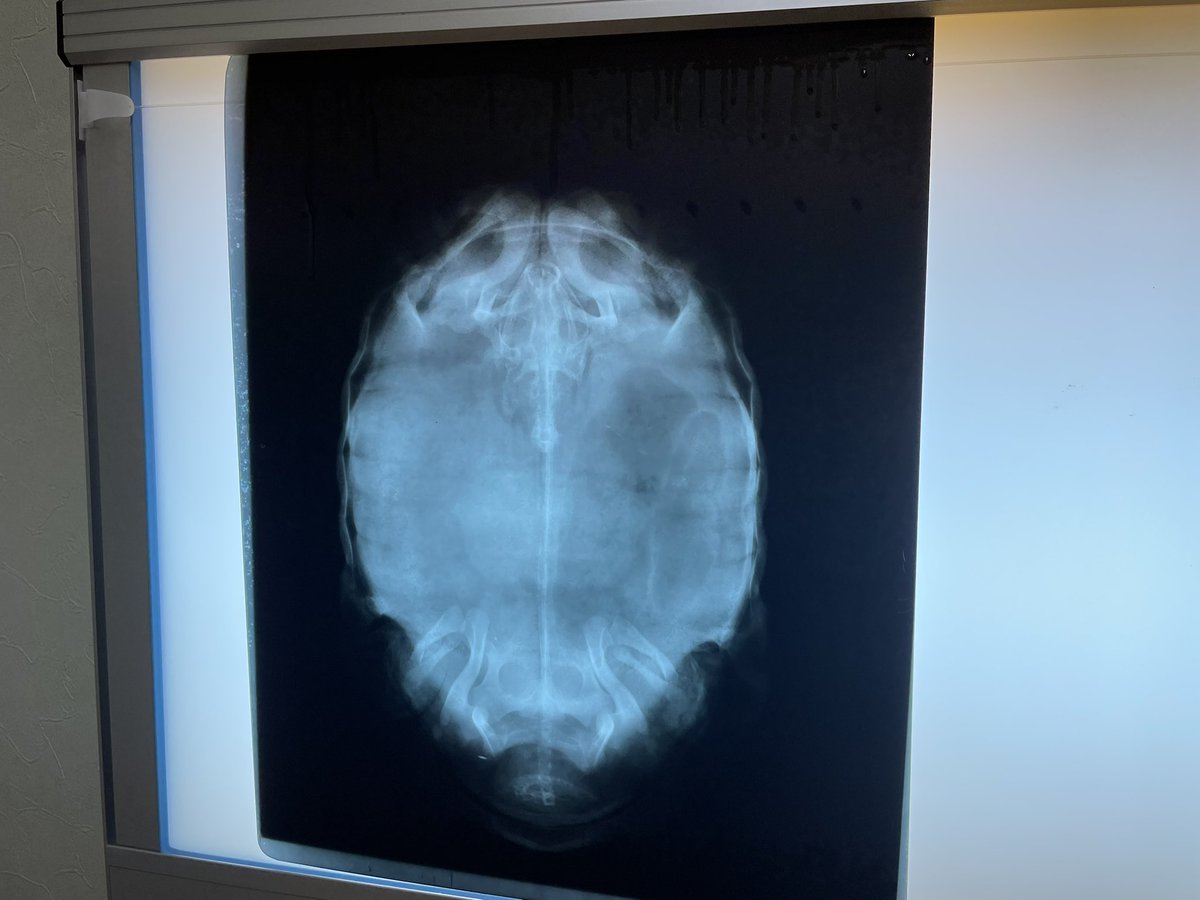

調子が悪いと思ったら、左の個体もめちゃくちゃ食石していました😓明日から投薬と温浴開始ですね💦 右の個体はあと少し🤏頑張れ👍 (レントゲン写真は左右逆になっています🙇) #ホウシャガメ #マダガスカルホシガメ

調子が悪いと思ったら、左の個体もめちゃくちゃ食石していました😓明日から投薬と温浴開始ですね💦

右の個体はあと少し🤏頑張れ👍

(レントゲン写真は左右逆になっています🙇)

#ホウシャガメ

#マダガスカルホシガメ